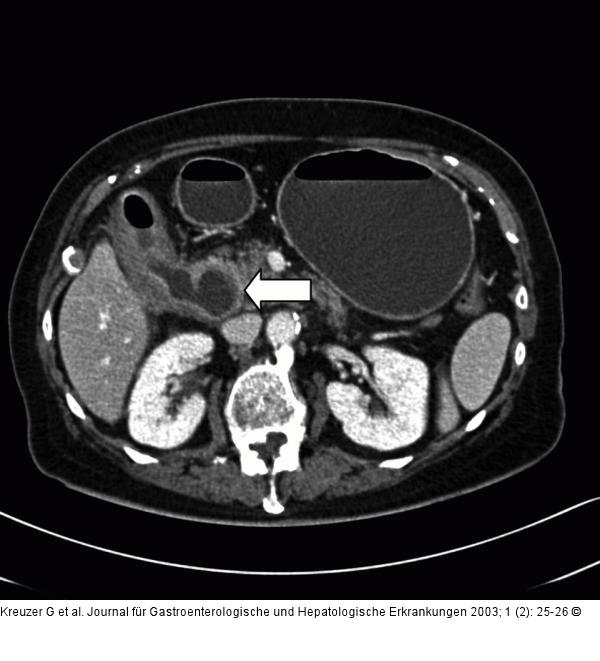

Abbildung 4: CT- Cholezystis CT: Cholezystojejunale Fistel (Pfeil). |